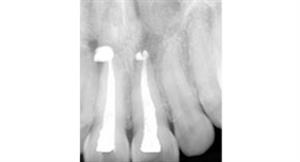

Root Canal Treatment

After